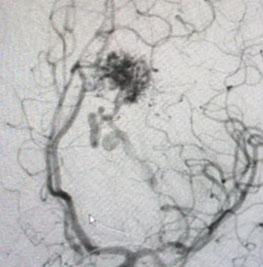

MRI was consistent with a left deep frontal AVM (Figure 2).

Fig. 2